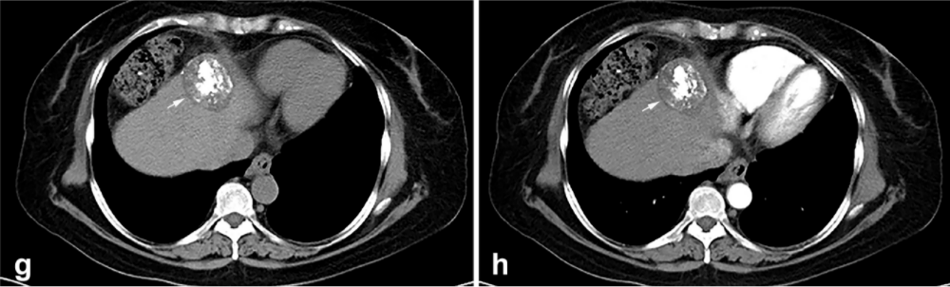

背景:由于一些原因,位于膈肌附近的腫瘤的熱消融在技術(shù)上具有挑戰(zhàn)性。首先,術(shù)中計(jì)算機(jī)掃描和超聲檢查無法清晰顯示射頻消融/微波消融切緣。第二,消融過程中不利的針分布和過熱可能導(dǎo)致肝包膜破裂,并對膈、肺和心臟造成嚴(yán)重?fù)p傷。第三,即使使用人工腹水,仍有9~22%的患者因肝周粘連或腫瘤位置靠近肝表面而導(dǎo)致膈肌熱損傷。冷凍消融可能是毗鄰膈肌的HCC的一種有前途的治療方法,因?yàn)樵谙谶^程中使用CT和US可以很好地顯示腫瘤邊緣。盡管一些研究評估了在高危區(qū)域使用冷凍消融治療HCC,但很少有研究針對膈肌臨近區(qū)域。

① 術(shù)后 1 月腫瘤治療反應(yīng):冷凍消融術(shù)后一個(gè)月腫瘤疾病控制率達(dá)95.9%。

③ 總生存曲線和局部腫瘤進(jìn)展曲線:冷凍消融后中位生存時(shí)間為 27.3 個(gè)月,中位局部腫瘤進(jìn)展時(shí)間為 20.9 個(gè)月。